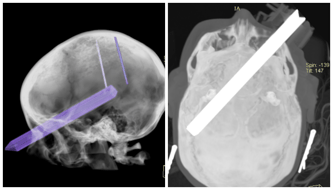

Cel zbiórki: rekonstrukcja czaszki, po wypadku

Ubytek 40% kości czaszki w wyniku wypadku.